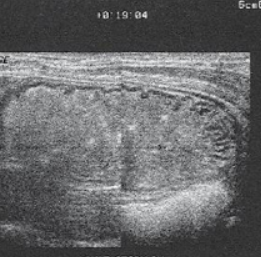

Pyloric Stenosis